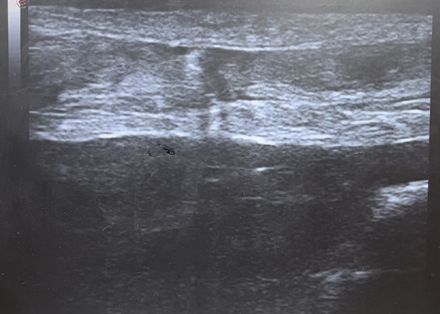

両側アキレス腱断裂

初回来院時

腱断端の接触

断裂したアキレス腱

腱弾端は十分に接触します